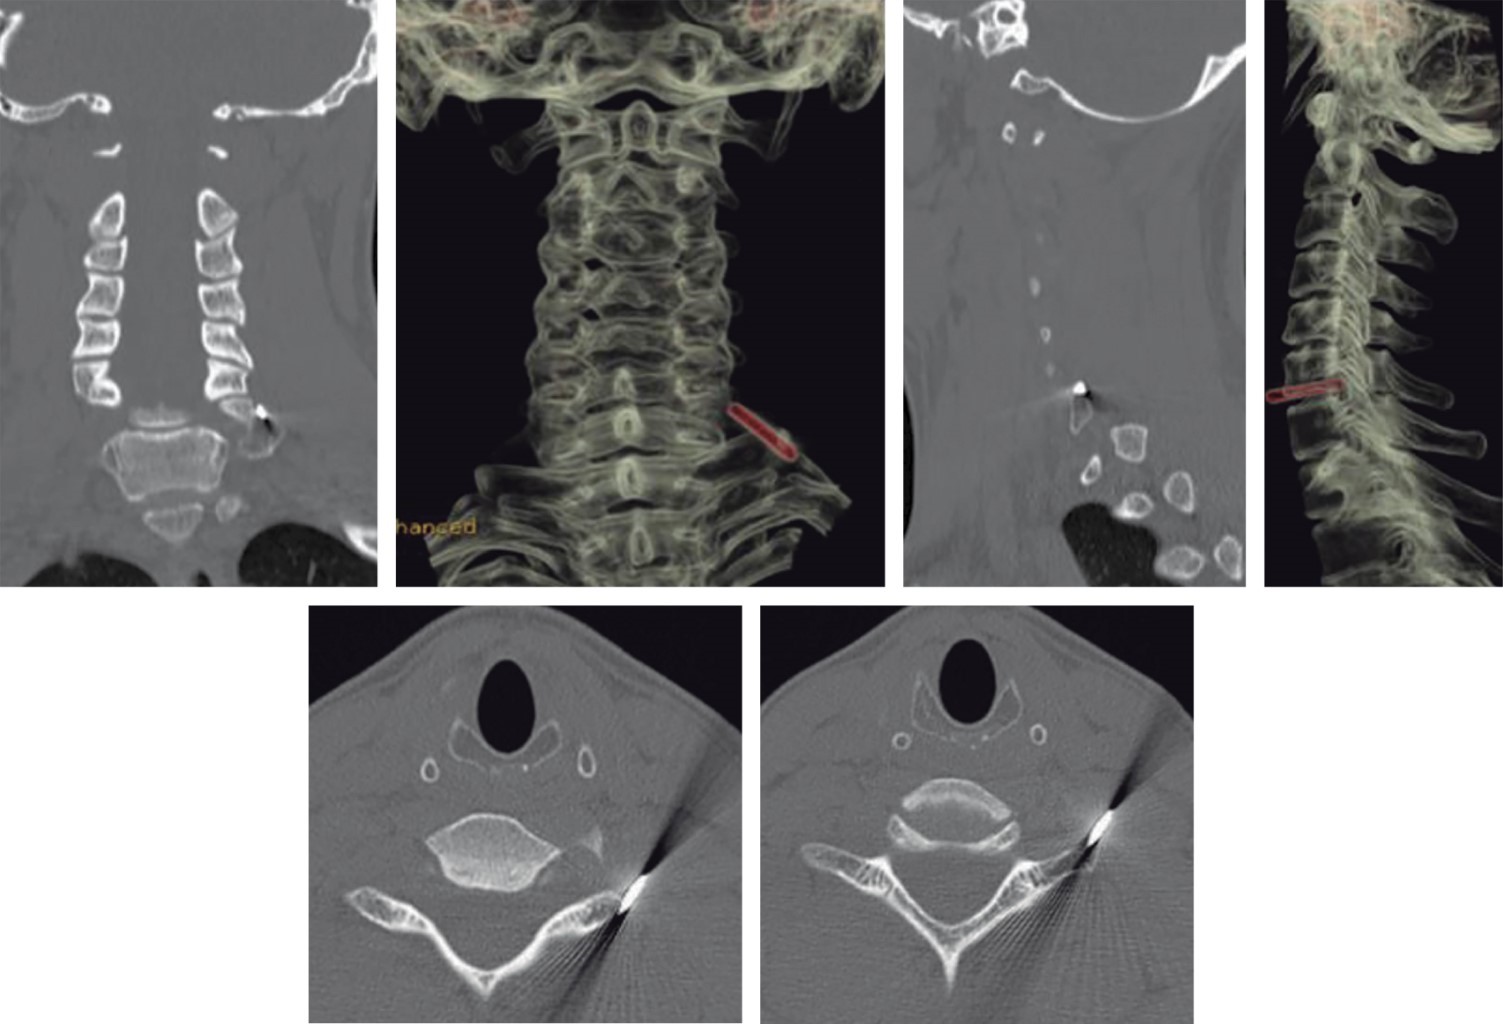

En radiografía anteroposterior (AP) de hombro derecho y radiografía anteroposterior de columna cervical se evidencia clavo Kirschner migrado a nivel del segmento C7-T1 (Figuras 1 y 2). En imágenes tomográficas se evidencia cuerpo extraño a nivel foraminal derecho (Figura 3).

Paciente masculino de 43 años de edad quien, cinco meses previos a la atención hospitalaria, presenta cervicalgia moderada sin sintomatología acompañante sin recibir atención médica. Siete días previos a la valoración y posterior a trauma contuso en región cervical y dorsal, presenta dolor intenso en región cervical, además de pérdida súbita de sensibilidad y fuerza motriz en cuatro extremidades. El paciente tiene como antecedente osteosíntesis de clavícula derecha con placas de reconstrucción y clavo Kirschner en institución privada hace ocho años. Al momento de la valoración actualmente reportada, se presenta movilizado en silla de ruedas, con tetraparesia, nivel neurológico C6, ASIA B. Se revisan radiografías anteroposterior y lateral de columna cervical en las que se evidencia clavo Kirschner en segmento C7-T1 (Figura 10). En tomografía computarizada se constata invasión de cuerpo extraño a conducto medular (Figura 11). Se realiza extracción quirúrgica de clavo Kirschner mediante abordaje supraclavicular derecho (utilizado para exploración de plexo braquial), se realiza disección neurovascular; se logra identificación directa de punta de clavo K mediante intensificador de imágenes. Se retira el clavo sin dificultad, no presentó fuga de líquido cefalorraquídeo (Figura 12A y B). El paciente en postoperatorio inmediato y a los 45 días posteriores a la cirugía no presenta cambios en estado neurológico.